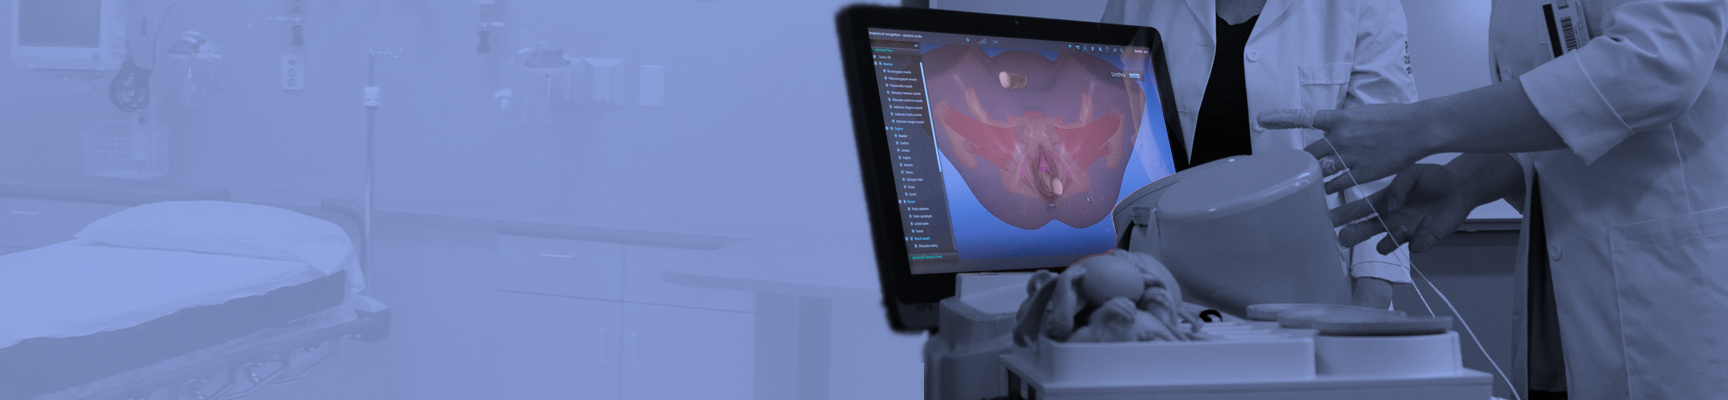

The World's Most Sophisticated Pelvic Simulator

No other pelvic anatomy and pelvic exam simulator provides the PELVIC Mentor’s level of realism and accuracy.

As a strong didactic tool, the PELVIC Mentor provides trainees with immediate feedback on anatomical recognition and the opportunity to practice pelvic exams accurately. The unique combination of the model’s anatomical structure, finger sensation and virtual model provide the most effective training tool to date, aimed at developing the physician’s confidence during pelvic examinations.